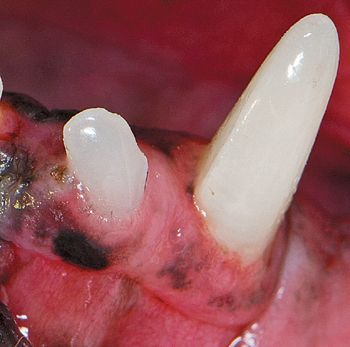

Keep in mind that eruption is controlled by genetic, environmental, infectious and traumatic factors.

The degree of severity of periodontal disease relates to a single tooth; a patient may have teeth that have different stages of periodontal disease. Here is an outline of the American Veterinary Dental College-approved periodontal disease classifications.